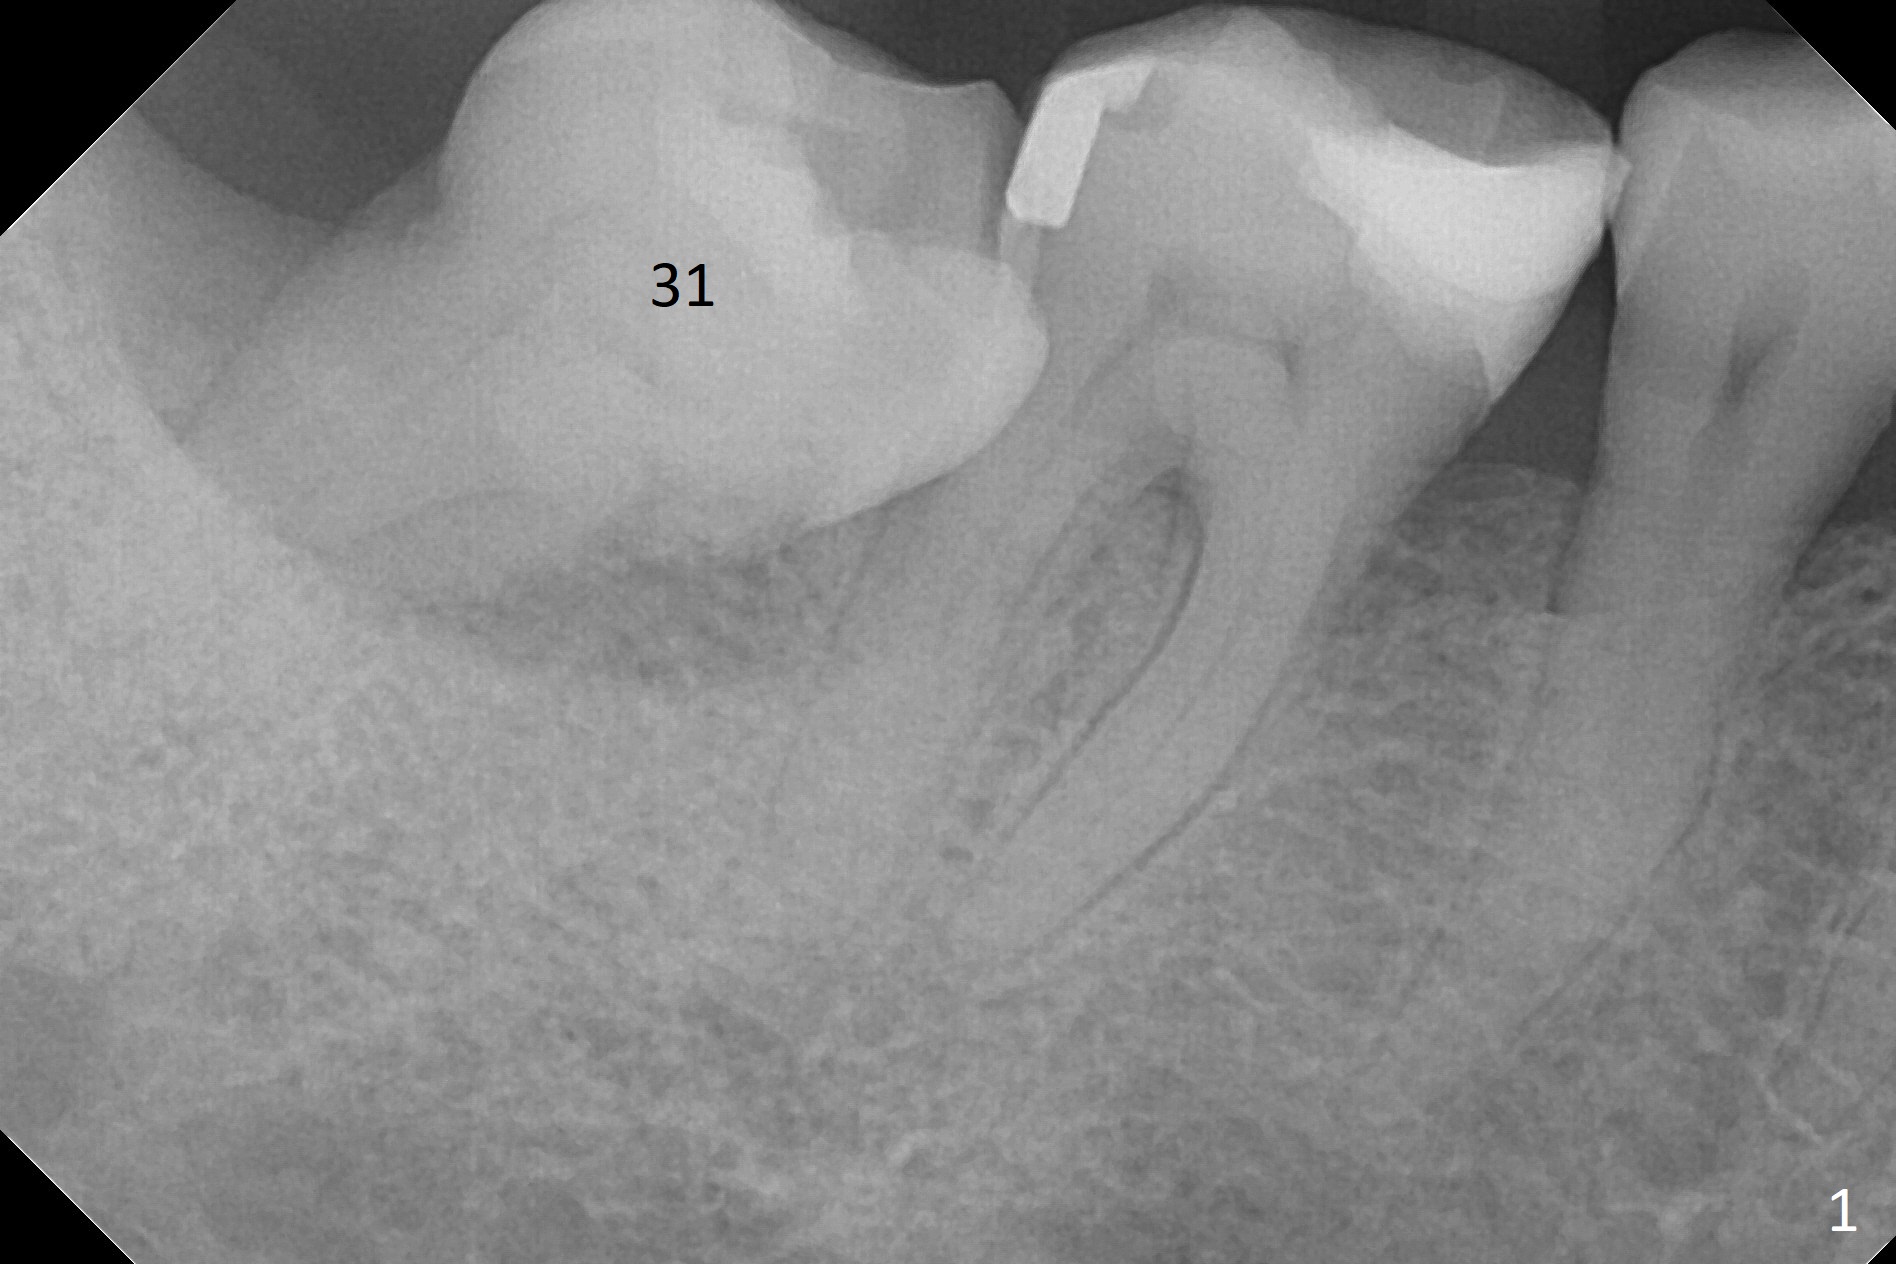

A 60-year-old man has chronic periodontitis, bruxism and malocclusion, e.g., #18 mesiolingual inclination (under occlusal trauma, Fig.1). The lingual pocket is deep with severe bone loss. After extraction, use implant positioner to gauze the size of the socket. Initiate osteotomy as mesial as possible and parallel to the 1st molar (Fig.2,3). Bone density is expected to be high. Prepare soft (1-piece) and hard (IS) tissue-level implants. The tooth remains loose 2 years later, although the patient is asymptomatic (Fig.4). Finally the tooth is symptomatic because of root tip fracture (Fig.5). Use drills with 7.3 mm stop for 4.5 or 5.0x8.5 mm implant free hand (Fig.6). The exposed implant will be covered with sticky bone (PRFx2). Prepare temporary and cemented abutments to hold bone graft in place.